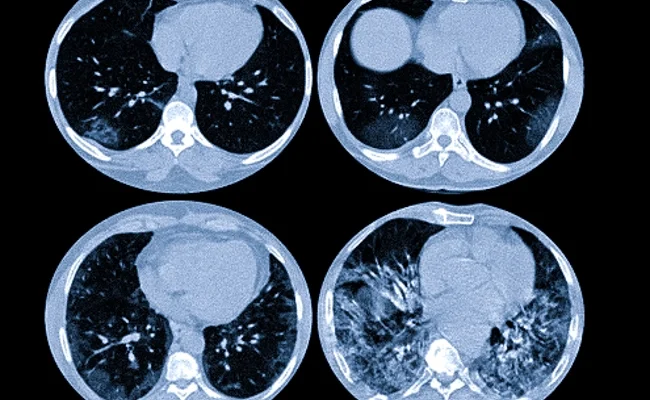

Методы раннего выявления легких заболеваний Заболевания легких представляют собой одну из самых серьезных угроз для здоровья человека. В связи с увеличением